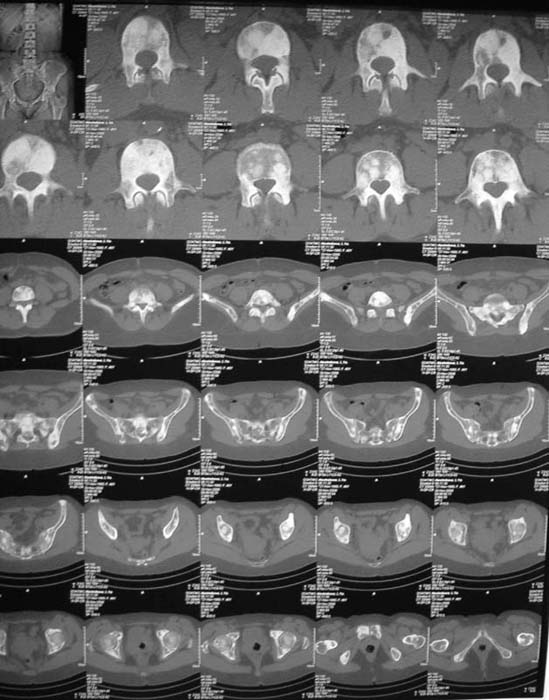

Женщина, 46 лет.

В течение четырех месяцев жалобы на боли в спине.

При МРТ (29.10.06) обнаружены диффузно-очаговые изменения в пояснично-крестцовом отделе позвоночника предположительно вторичного характера.

В октябре 2006 г. по поводу маточного кровотечения (менопауза 4 мес.) выполнено УЗИ - гиперплазия эндометрия, полипоз. Операция - удаление полипа, выскабливание полости матки. Цитологический анализ - пласты переходного климактерического эндометрия.Проведено комплексное исследование. В приложении: рентгенограммы и томограммы поясничного отдела позвоночника; радиологические исследованиямолочной железы, ЖКТ, почек, грудной клетки, анализы.УЗИ (18.12.06.) щитовидной железы, молочных желез - без патологии (умеренный фиброз по ходу млечных протоков).

Остеосцинтиграфия 4.12.06. - активный остеобластический процесс в поясничном, нижнегрудном отделах позвоночника, костях таза.Местными онкологами онко-процесс исключен. Фтизиатрический и онкогематологический диагнозы исключены.

Вопросы: 1. Диагноз? 2. Методы дополнительной диагностики? 3. Тактика лечения?

Диагноз, исходя из сцинтиграфии, предположительно метастазирование без определения первичного очага. Я сделал бы КТ органов и костей таза. Следующим шагом желательно взять биопсию, возможно из крыла таза (будет проще) после четкой визуализации очагов на КТ...